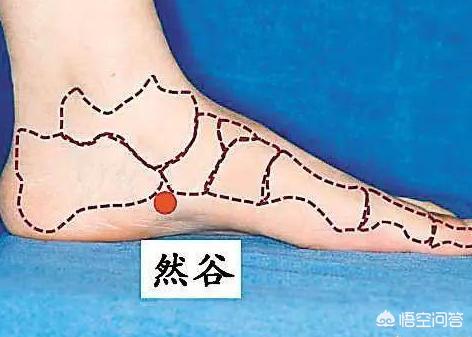

Touchez l'os interne de la cheville du pied avec votre main, et il y aura un os élevé à 2 cm en diagonale devant vous, et le bord inférieur de cet os élevé est l'acupoint Ranggu.

Le point Ranggu étant situé à un endroit où l'essence est cachée plus profondément, il est important de presser ce point avec une force appropriée, puis de le relâcher lorsqu'une sensation de douleur et de gonflement se fait sentir, puis de le presser à nouveau et de le relâcher à nouveau.

Il faut donc répéter l'opération 15 à 20 fois, appuyer sur un pied puis changer l'autre pied, adhérer à une période de temps, peut soulager et traiter efficacement la sécheresse de la bouche, l'urgence urinaire fréquente et d'autres symptômes.